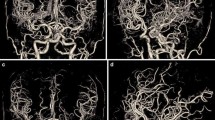

Representative cases are shown in Figs. 2, 3, and 4. Figure 2 shows the case of a 71-year-old woman with a left MCA aneurysm who underwent BSCTA under both the 120-kVp and the 80-kVp protocols after 6 months. Although the radiation and the CM doses of the 80-kVp scans were substantially lower than those in the 120-kVp protocol (CTDIvol: 14.8 vs 41.8 mGy; CM dose: 51 vs 65 ml), the image quality of the 80-kVp scan was better than that of the 120-kVp scan. Figure 3 shows the 80-kVp images of a 73-year-old woman who had undergone clipping of a right ICA aneurysm (CTDIvol: 16.4 mGy; CM: 38 ml). Arteries around the skull base and clip were obscured on the non-subtraction images. They were clearly depicted on subtraction images without severe clip-induced artifacts or confounding contrast enhancement of the cavernous sinus. Figure 4 shows the 80-kVp images of an 81-year-old woman with a clipped left MCA aneurysm (CTDIvol: 16.2 mGy; CM: 32 ml). The ICA at the level of the skull base and the aneurysm remnant at the left MCA, obscured on the non-subtraction image, were clearly depicted on the subtraction image.

A 73-year-old woman who had undergone clipping of a right ICA aneurysm was scanned with the 80-kVp protocol (iopamidol-370, 38 ml; CTDIvol: 16.4 mGy). The upper panel shows the non-subtraction slab-MIP (left) and subtraction MIP with clip (middle) and without clip (right). The lower panel shows volume-rendered images of non-subtraction (left) and subtraction with clip (middle) and without clip (right). Arteries around the skull base and clip were obscure on the non-subtraction image. They were clearly depicted on subtraction images without severe clip-induced artifacts or confounding contrast enhancement of the cavernous sinus